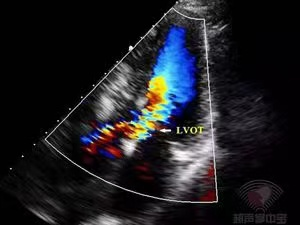

心尖五腔心切面CDFI:左室流出道呈五彩镶嵌花色血流信号。

心尖五腔心切面CW:左室流出道最大瞬时流速和压差增大(Vmax:462cm/s,PG:85mmHg),频谱峰值后移。CW示左室流出道峰值流速462cm/s,PG:85mmHg。

术前彩色多普勒超声心动图